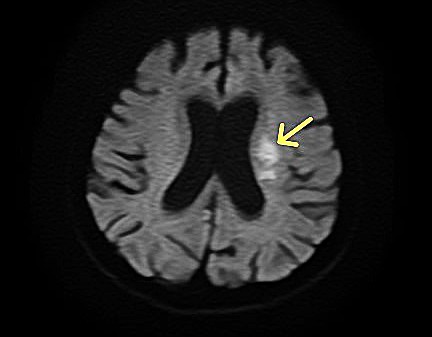

脳MRI・MRA検査

MRI(磁気共鳴画像)とMRA(磁気共鳴血管画像)を用いて、脳の断面や血管の状態を詳しく確認する検査です。

痛みや放射線被ばくの心配がなく、寝ているだけで脳の健康状態を調べることができます。

自覚症状のない小さな病変の早期発見を目指します。

脳MRI・MRA診断画像2

この検査でわかること

• 脳出血の原因となる血管の異常

• 脳腫瘍の有無

• 加齢や認知症に伴う脳の変化

• 自覚症状のない小さな脳梗塞の跡